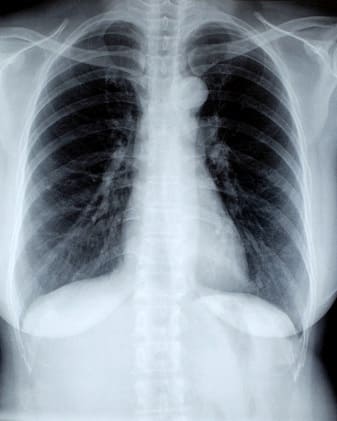

Ofrecemos una variedad de radiografías digitales, adecuadas para diferentes necesidades diagnósticas, realizadas con equipos de última generación.